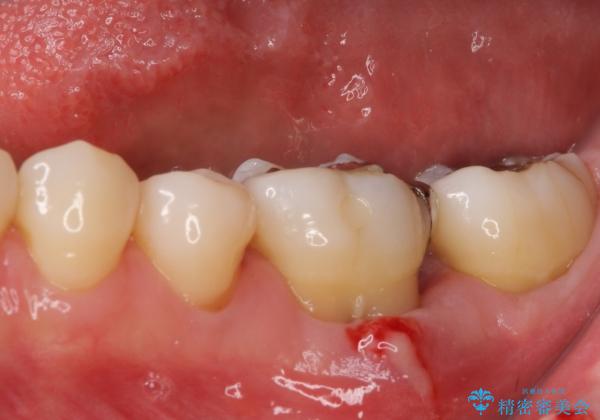

根管治療を終えた後には、今まで気になっていた痛みが消え、快適に日常生活を送れるようになりました。

痛みが取れるとともに、気になっていた大きな銀歯も自然なセラミックとなり、患者様には大変満足していただけました。